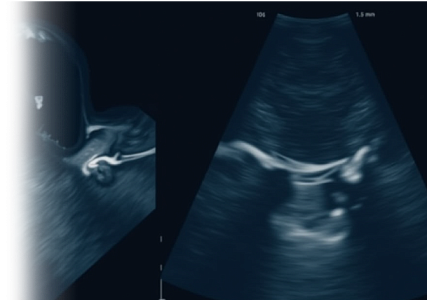

УЗИ на ранних сроках беременности

УЗИ на ранних сроках беременности (1 триместр) – ультразвуковой метод исследования, который позволяет не только подтвердить наличие беременности, но и предоставить ценную информацию о развитии плода и здоровья будущей мамы, выявить различные патологии и заболевания, что помогает своевременно принять меры по их лечению и предотвращению.

УЗИ-скрининг на 1 триместре беременности

УЗИ-скрининг 1 триместра беременности – ультразвуковой метод исследования для оценки здоровья плода и выявления возможных патологий.

УЗИ-скрининг на 2 триместре беременности

УЗИ-скрининг 2 триместра беременности – ультразвуковой метод исследования для оценки здоровья плода, его соответствия гестационному сроку и выявления возможных патологий.

УЗИ-скрининг на 3 триместре беременности

УЗИ-скрининг 3 триместра беременности – ультразвуковой метод исследования для оценки здоровья плода и выявления возможных патологий.